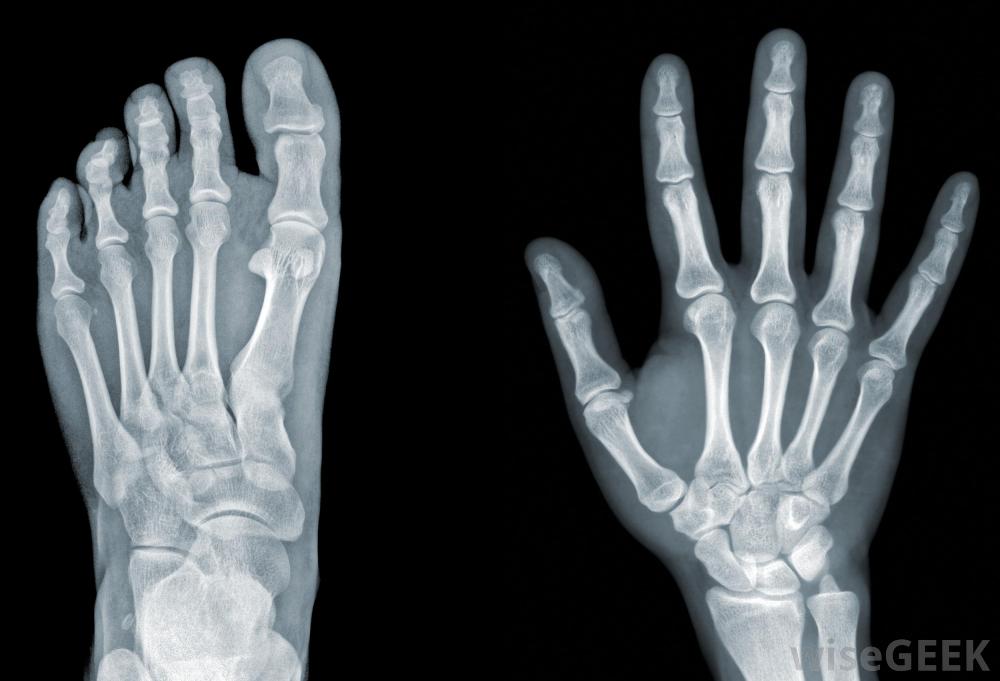

North Canterbury X-ray (NCX) operates a highly-professional medical X-ray clinic in the centre of Rangiora – a locally owned and operated service with dedicated staff, working efficiently with your own GP to bring you fast and friendly attention and results just when you need it most. Easy parking – no need to travel to the city!